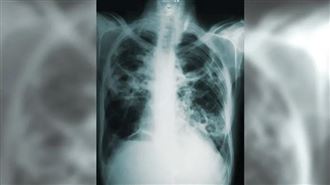

汪建民肺腺癌逝! 醫揭「罹癌元凶」:男比女更難治

藝人汪建民去(2023)年檢查罹患肺腺癌第四期,歷經長期治療,仍在昨(7)日病逝。胸腔內科醫師蘇一峰發文說明,肺腺癌是台灣較常見的癌症之一,空污和罹癌有很大的關聯性;若不幸罹癌,有標靶藥物可以使用,治療成功率較高,據臨床觀察,有標靶突變基因...

藝人汪建民在去年的7月時候,發現罹患了肺腺癌第四期,癌細胞擴散到頸椎、腦內,已接受長達7個月的化療,經過治療還一度復出工作,沒想到,7日汪建民的妹妹證實,因肺腺癌離世,享年56歲。對此,擁有胸腔內科專長的蘇一峰醫師表示,國人最常罹患的是肺腺...